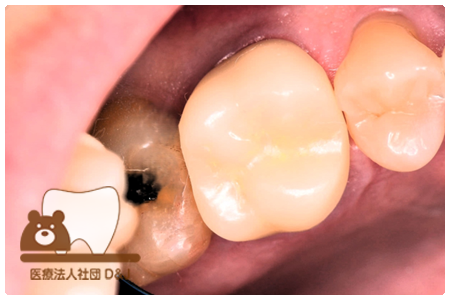

症例4フルジルコニアクラウン 左下6

治療前

治療後

37歳 男性

- 治療内容

- 以前のクラウンがセメントの劣化により外れた為その上にフルジルコニア製の被せ物を装着しました。見た目と強度を両立した自由診療の治療です。

- 治療期間

- 1カ月

- 費用

- 自費

フルジルコニアクラウン:77,000円(税込)

(R8.1月時点)

- その他の治療の費用は含まれておりません。

- リスク・副作用

- 硬い素材のため、かみ合う歯に負担がかかることがあります。将来取り外す場合に歯に負担がかかることがあります。強い力が加わると、まれに欠けたり割れたりすることがあります。